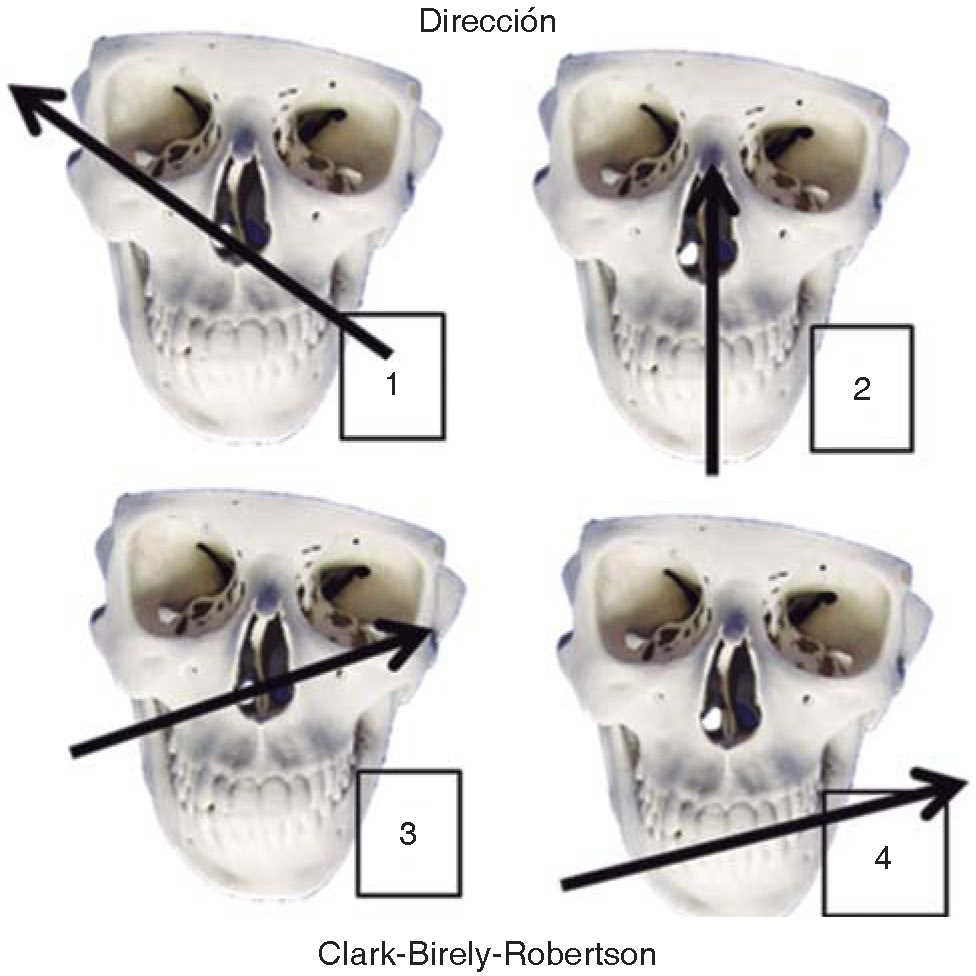

Se determinan las lesiones provocadas por el arma de fuego, y se crea una guía para el manejo definitivo de estos defectos. Existen múltiples clasificaciones, aunque nosotros nos basamos en cuatro de ellas: la primera distingue tres tipos en función del patrón de entrada y salida del proyectil, encontrándonos lesiones penetrantes (sólo orificio de entrada); lesiones perforantes (orificio de entrada y salida), segunda: por armas de pequeño calibre y larga distancia; por lesiones avulsivas provocadas por armas a una distancia muy corta con balas deformantes que generan gran pérdida de sustancia, tercera descrita por Clark- Birely-Robertson que describen cuatro trayectorias comunes del proyectil a nivel facial (Figura 3)9 y cuarta clasificación en lesiones de bajo y alto grado de energía, en relación a la pérdida de sustancia y lesiones provocadas en la cara.16